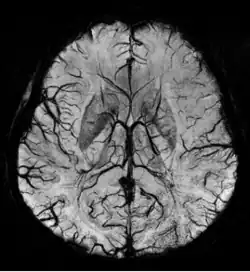

Susceptibility weighted imaging (SWI), originally called BOLD venographic imaging, is an MRI sequence that is exquisitely sensitive to venous blood, hemorrhage and iron storage. SWI uses a fully flow compensated, long echo, gradient recalled echo (GRE) pulse sequence to acquire images. This method exploits the susceptibility differences between tissues and uses the phase image to detect these differences. The magnitude and phase data are combined to produce an enhanced contrast magnitude image. The imaging of venous blood with SWI is a blood-oxygen-level dependent (BOLD) technique which is why it was (and is sometimes still) referred to as BOLD venography. Due to its sensitivity to venous blood SWI is commonly used in traumatic brain injuries (TBI) and for high resolution brain venographies but has many other clinical applications. SWI is offered as a clinical package by Philips and Siemens but can be run on any manufacturer's machine at field strengths of 1.0 T, 1.5 T, 3.0 T and higher.

SWI uses a fully velocity compensated, RF spoiled, high-resolution, 3D gradient recalled echo (GRE) scan. Both the magnitude and phase images are saved, and the phase image is high pass (HP) filtered to remove unwanted artifacts. The magnitude image is then combined with the phase image to create an enhanced contrast magnitude image referred to as the susceptibility weighted (SW) image. It is also common to create minimum intensity projections (mIP) over 8 to 10 mm to better visualize vein connectivity. In this way four sets of images are generated, the original magnitude, HP filtered phase, susceptibility weighted, and mIPs over the susceptibility weighted images.